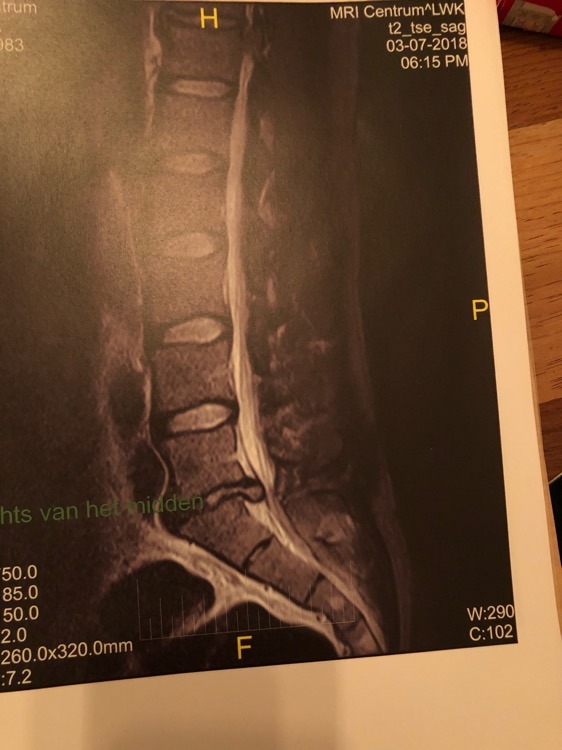

lekkerding! Wie weet ben je over 2 weken al aan het revalideren en is het ergste achter de rug! (Pun intended

)